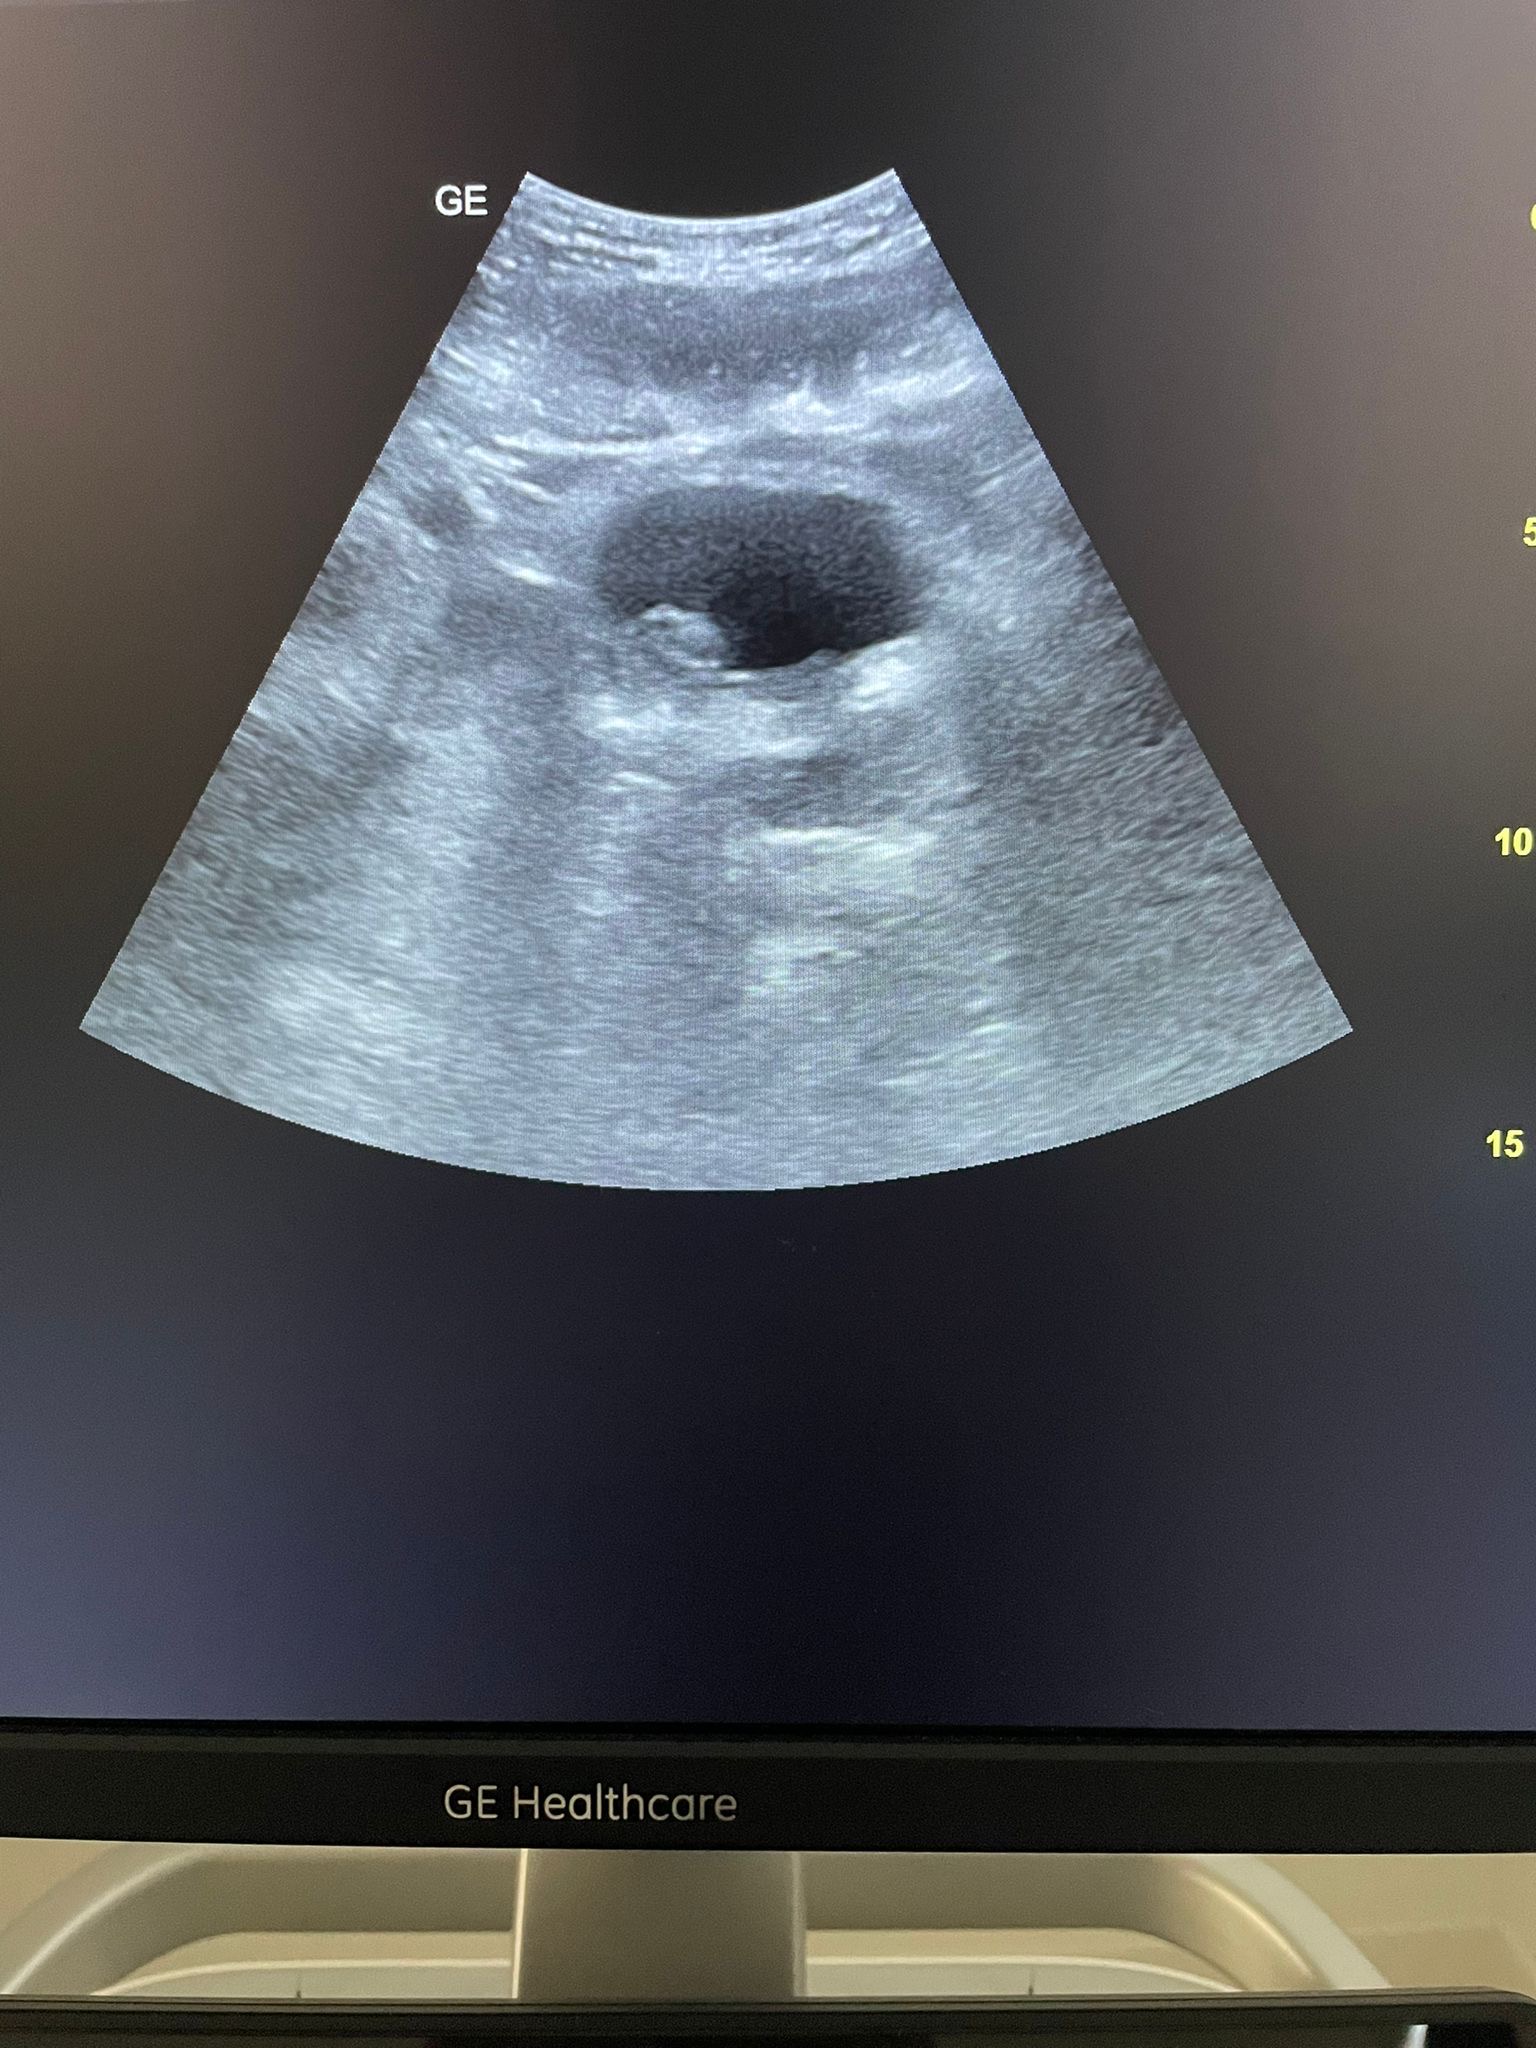

Hallazgos ecográficos

Se realiza ecografía abdominal donde se observa vejiga de adecuada repleción con imagen polipoide de 21x13 mm a nivel del piso vesical, discretamente a la derecha con signos de vascularización al examen doppler color. Se realiza URO-TC de abdomen y pelvis cuya conclusión es: microlitiasis renales bilaterales de 3-3,5 mm no obstructivas. Uréteres sin dilatación. Lesión intraluminal vesical de 15 mm en pared lateral derecha, cercana a la unión ureterovesical, con engrosamiento urotelial adyacente, de alta sospecha de neoplasia urotelial; menos probable coágulo organizado o pólipo inflamatorio dada la morfología y la ausencia de densidad cálcica. Sin adenopatías ilíacas o inguinales significativas.